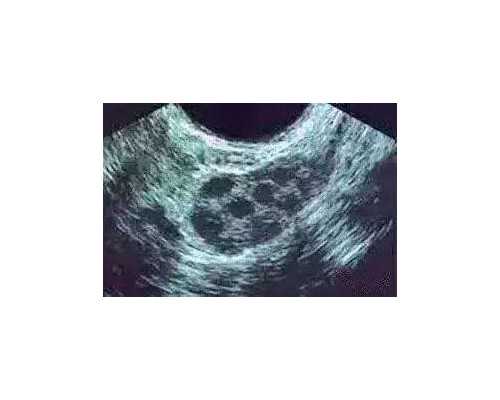

第三代试管婴儿技术的到来,也让许多高龄女性看到了再次生育的福音,这项技术能够排除遗传疾病、挑选健康胚胎进行移植,让宝宝的健康状况更佳,这也促使更多人开始选择第三代试管技术。从事泰国三代试管婴儿服务已经15余年,目前跟当地好几家资深三代试管婴儿医院均有合作,选择三代试管婴儿能够让您成功获得好孕。wzz

第三代试管婴儿可以选择性别吗?做一次大概费用是多少?在医疗水平还没有那么发达的时候,你只能等到出生那天才能知道一个未出生的孩子的性别。

随着科技的发展和医疗水平的进步,如果想知道胎儿的性别,只需要在胎儿到某个月的时候去医院做个b超就可以知道性别了。但是,这仅限于医生的知识,父母和其他人无权知道胎儿的性别。

准确的说,从技术角度来说,第三代试管婴儿是可以选择性别的。

而在我国,按照有关部门的规定,医院第三代试管婴儿手术是不允许选择性别的,除非夫妻双方有一些遗传病(比如男女传播或者男女传播),才可以去医院做第三代试管婴儿手术。这样医生就可以通过第三代试管婴儿手术来选择胎儿的性别,让夫妻生下健康的宝宝。